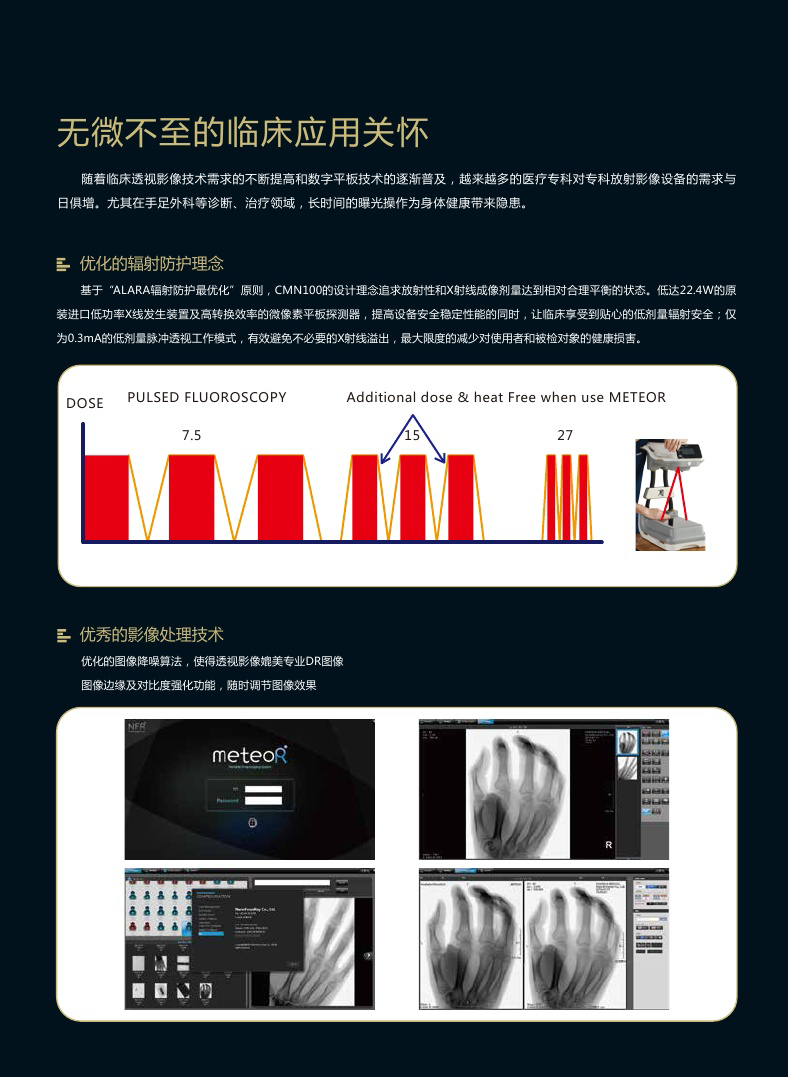

低剂量脉冲透视技术

基于“ALARA 辐射防护最优化”原则,CMN100 的设计理念追求放射性和 X 射线成像剂量达到相对合理平衡的状态。

低达 22.4W 的原装进口低功率 X 线发生装置及高转换效率的微像素平板探测器,提高设备安全稳定性能的同时,让临床享受到贴心的低剂量辐射安全;

高达 0.3mA 的低剂量脉冲透视工作模式,有效避免不必要的 X 射线溢出,最大限度的减少对使用者和被检对象的健康损害

帧数在 7.5FPS 到 27PFS 之间 & 有效脉宽控制在 30~100%之间

脉冲透视操作的总剂量比连续透视操作模式低 35~80%